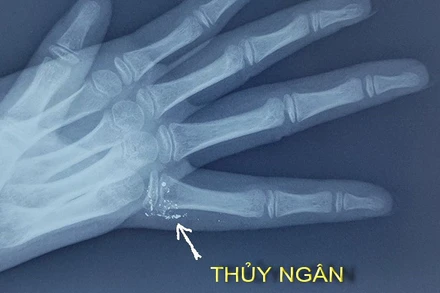

Bệnh viện Bạch Mai đang điều trị cho một cháu bé bị nhiễm độc thủy ngân qua da khi người nhà vẩy nhiệt kế thủy ngân và không may chọc vào tay trẻ.